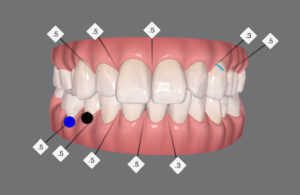

🔶アフター🔶

正面

右

予想通り

右上の歯がグラグラしてきたので

次回は ここにインプラント

続く